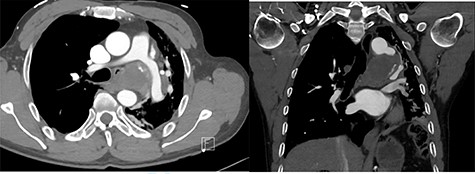

On presentation, chest X-ray illustrated a prominent proximal descending thoracic aorta contour and a completely collapsed left lung (Fig. 1). On computed tomography angiogram (CTA), the patient was found to have a large saccular aneurysm measuring 5.0 × 5.0 × 5.0 cm in size, arising from a focal location of the proximal descending thoracic aorta distal to the origin of the left subclavian artery with evidence of contained rupture (Fig. 2). The mass was found to be causing significant external compression of the left main bronchus leading to significant effacement of the left main primary bronchi leading to extensive collapse in both left upper and lower lobes and overall reduction in volume of the left hemithorax (Fig. 3).